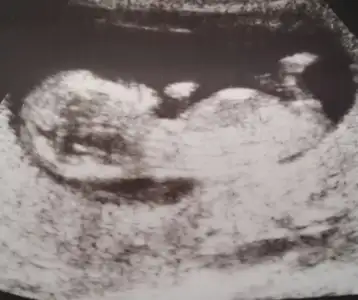

kız gibi duruyor canımm ama bir çoğunda tutmuyor gibi son dönemde doktor bi tahminde bulundu muMerhaba cinsiyet hakkında yorum yapabilecek olan var mı

Nub dan anlayan var mı![]()

Büyük ihtimal kiz dedi teşekkür ederimkız gibi duruyor canımm ama bir çoğunda tutmuyor gibi son dönemde doktor bi tahminde bulundu mu